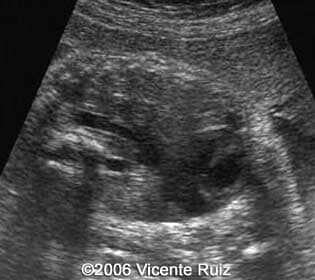

Axial views of the chest showing the left hemithorax occupied by an heterogeneous mass

Note the absence of the stomach in the axial section of the abdomen